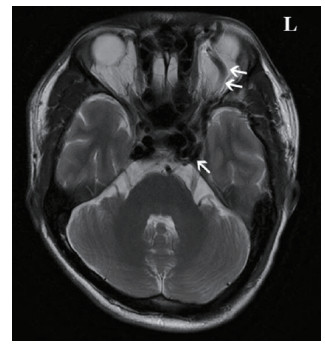

2.1 临床表现本研究中CCF患者出现眼球突出141例(97.91%)、球结膜充血140例(97.22%)、颅鸣105例(72.92%)、视力下降99例(68.75%)以及复视36例(25.00%)症状,见图 1。查体可见眼球突出、球结膜充血水肿,眼球运动障碍;眶周可闻及血管杂音,Matas试验阳性。脑部血管影像学检查,全部患者可见眼部静脉异常增粗[8],见图 2。

| 图 2 双箭头显示了异常增粗的左侧眼上静脉,单箭头处显示了扩张的海绵窦 Fig 2 Double arrows show abnormally thickened left superior ophthalmic vein, single arrow shows dilated cavernous sinus |